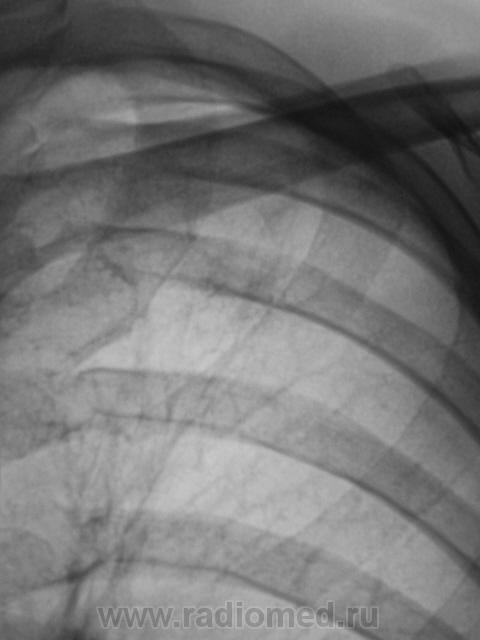

Динамика через 2 месяца после специфического лечения.

Пациент прислан был на контроль. Первично, был выявлен после прохождения профилактической флюорографии.

Ниже снимки до лечения.

Валентин Львович! Динамика, конечно, слабая. Но "Его Величество" не всегда адекватно реагирует на проводимую терапию. Или это изменения после перенесенного "Его Величества".  Склоняюсь к мысли слабо положительной динамики после проводимой специфической терапии.

Спасибо за высказанное мнение. Мы тоже отметили некоторую положительную динамику.

Считаю, что динамики нет - как был Твс-архив, так и остался...

Пневмосклероз без динамики. Очаговых изменений не видно. Неужели подтвержден туберкулез?

При первичном обследовании туберкулёз подтвержден. Подтвержден и посевом на средах.